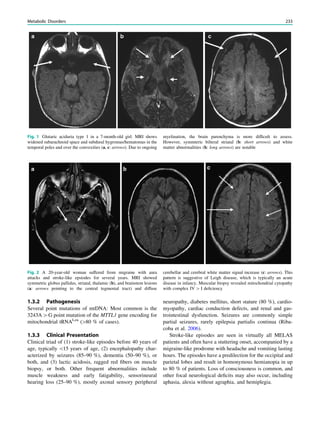

Fig. 1 Digital photogram of the brain surface before placement of a

results of electrical stimulations and ictal/ intraictal EEG activity. Blue

grid contacts represent the eloquent zone, which is the motor cortex in

this case. The black area represents the epileptogenic lesion, defined

as the radiographic lesion that causes the seizures. The yellow area is

the seizure onset zone, defined as the area from which the clinical

seizures are generated. The seizure onset zone is often, but not

necessarily, congruent with the epileptogenic zone, defined as the

cortex area indispensable for the generation of seizures

Fig. 2 Epileptogenic lesion and symptomatogenic zone. A 40-year-

old woman suffered from complex focal seizures with a fearful face

and body rocking. The symptoms thus pointed to the mesial frontal

lobe as the origin. MRI shows right-sided hippocampal sclerosis

(a, arrow). Simultaneous video and EEG recordings from interhemi-

spheric (c) and convexity strip and intrahippocampal depth (b) elec-

trodes show seizures starting in the right hippocampus (d, arrow).

Clinical symptoms start around 1 s afterwards (d, asterisk)